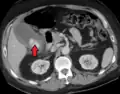

Acute cholecystitis as seen on CT. Note the fat stranding around the enlarged gallbladder.

Right upper quadrant abdominal ultrasound is most commonly used to diagnose cholecystitis.[1][26][27] Ultrasound findings suggestive of acute cholecystitis include gallstones, pericholecystic fluid (fluid surrounding the gallbladder), gallbladder wall thickening (wall thickness over 3 mm),[28] dilation of the bile duct, and sonographic Murphy's sign.[13] Given its higher sensitivity, hepatic iminodiacetic acid (HIDA) scan can be used if ultrasound is not diagnostic.[13][14] CT scan may also be used if complications such as perforation or gangrene are suspected.[14]